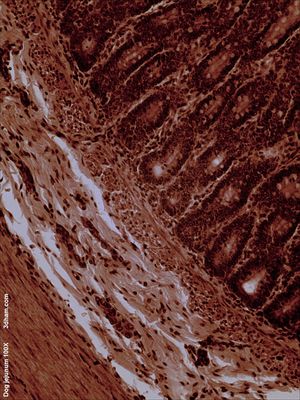

빈창자의 내부 표면은 섭취된 음식에 노출되어 있으며, 융모라고 하는 손가락 모양의 점막 돌기로 덮여 있다. 이 융모는 섭취한 음식물로부터 영양소를 흡수할 수 있는 조직의 표면적을 증가시킨다. 이 융모를 덮는 상피 세포에는 미세융모가 있다. 빈창자와 돌창자를 통한 상피 세포를 가로지르는 영양소 수송에는 설탕 과당의 수동 수송과 아미노산, 작은 펩타이드, 비타민, 대부분의 포도당의 능동 수송이 포함된다. 빈창자의 융모는 십이지장이나 돌창자의 융모보다 훨씬 길다.[1]빈창자의 pH는 일반적으로 7에서 8 사이(중성 또는 약간 알칼리성)이다.[1]

빈창자와 돌창자는 장간막에 의해 매달려 있어 복강 내에서 장의 큰 이동성을 부여한다. 또한 원형 및 종 방향의 민무늬근을 포함하여 연동 운동으로 알려진 과정을 통해 음식을 이동시키는 데 도움이 된다.[1]

빈창자는 브루너샘(십이지장에서 발견됨)이나 페이어판(돌창자에서 발견됨)이 거의 없다. 하지만, 장간막에 몇 개의 빈창자 림프절이 매달려 있다. 빈창자는 영양소 흡수를 위한 표면적을 늘리는 점막하층의 큰 원형 주름인 원형 주름이 많이 있다. 원형 주름은 빈창자에서 가장 잘 발달되어 있다.[1]

빈창자와 돌창자 사이에는 경계선이 없다. 그러나 미묘한 조직학적 차이점이 있다.[1]

- 빈창자의 융모는 길고 손가락 모양의 돌출부처럼 보이며, 조직학적으로 식별 가능한 구조이다.[1]